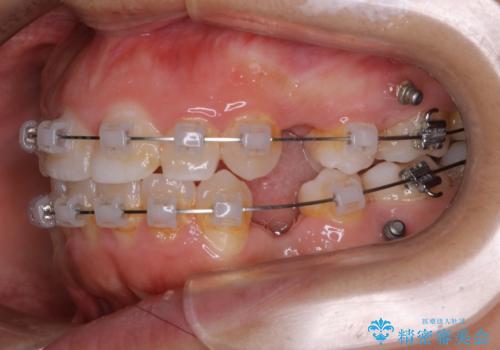

- 矯正装置

- ワイヤー(クリア装置)

- 治療期間

- 2年6ヶ月

- 30回以上

- 治療計画

しっかりと口元・顔貌まで変化を起こせるように上下左右の第一小臼歯を抜歯し、ワイヤー装置にて矯正を開始することとなりました。

- 税込¥990,000 (ワイヤー装置+マイクロインプラント費用)費用は治療当時の料金となります